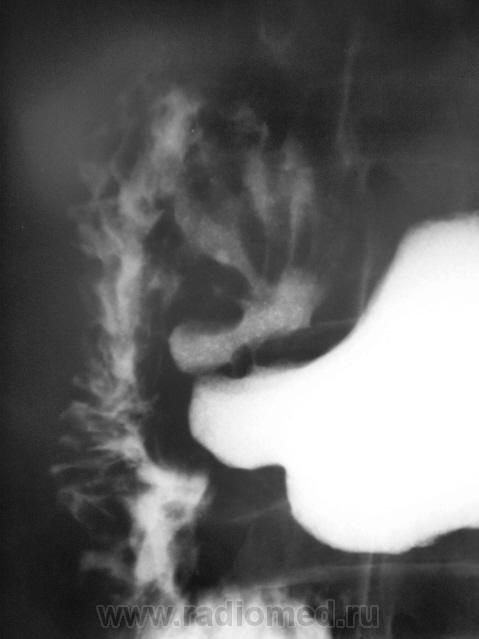

Катенёв Валенти... Дата публикации 19.01.2010, 23:20 Согласуясь, с закономерностью В.А. ФАНАРДЖЯНА, Как можно назвать такие деформации? Сб, 23/01/2010 - 23:41 #1 DR.RAD Не на сайте Был на сайте: 11 лет 11 месяцев назад Зарегистрирован: 25.03.2009 - 18:22 Публикации: 805 1 и 2 снимки, когда образуется карман на латеральном контуре при язве задей стенки луковицы, на 3 и 4 снимках деформация луковицы ( карманы на латеральном и медиальном контурах) при язве на передней и задней стенках луковицы.

1 и 2 снимки, когда образуется карман на латеральном контуре при язве задей стенки луковицы, на 3 и 4 снимках деформация луковицы ( карманы на латеральном и медиальном контурах) при язве на передней и задней стенках луковицы.